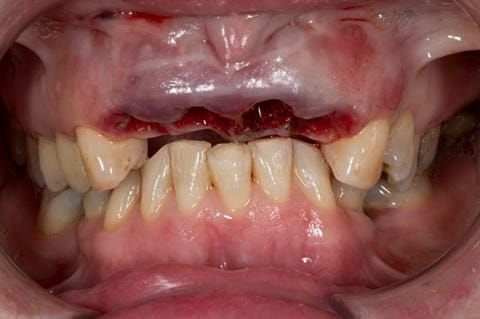

- UR2 peri-radicular periodontitis with a peri-radicular area on the root apex. Retrograde amalgam filling from a previous apicectomy. No visible root canal or root canal filling. Large circumferential marginal gap between the crown and tooth. Large post and core present. Very little tooth structure remaining resulting in a fragile tooth with increased potential for fracture.

- UR1 peri-radicular periodontitis with a small peri-radicular area on the root apex with wide blunderbuss apex. Radio-opaque root canal filling present approximately 3 mm short of the radiographic apex. Large circumferential marginal gap between the crown and tooth. Large post and core present. Very little tooth structure remaining resulting in a fragile tooth with increased potential for fracture.

- UL1 peri-radicular periodontitis with a peri-radicular area on the root apex. Retrograde amalgam filling from a previous apicectomy. Visible root canal space with no sign of root canal filling. Large circumferential marginal gap between the crown and tooth. Large post and core present. Very little tooth structure remaining resulting in a fragile tooth with increased potential for fracture.

- UL2 peri-radicular periodontitis with a peri-radicular area on the root apex. No visible root canal or root canal filling. Large circumferential marginal gap between the crown and tooth. Large post and core present. Very little tooth structure remaining resulting in a fragile tooth with increased potential for fracture.

- High smile line showing gum above gingival zeniths of upper front teeth when smiling. Aesthetic failure of the upper four incisors with inflammation of the gingivae and mis-match of the gingival zenith levels.

Following consultation and second discussion appointment the patient chose to have option 3 namely, a maxillary cobalt chromium based partial denture/protective occlusal splint. The clinical situation and treatment process is shown in detail below with photographs. The patient was successfully rehabilitated with this and her quality of life considerably improved. The clinical work was provided by Finlay and the technical work by Rowan.